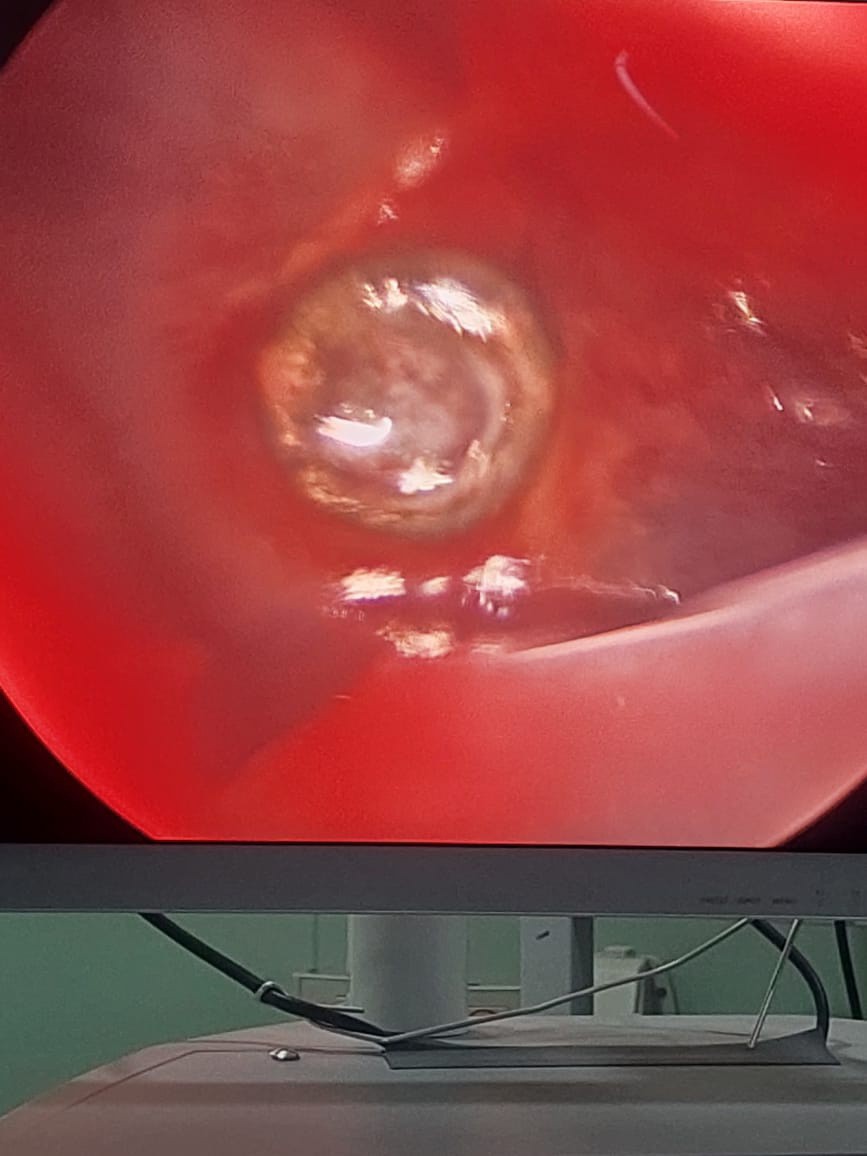

وعقب ذلك، نُقلت المريضة إلى غرفة العمليات، حيث أُجريت جراحة دقيقة لاستخراج الرصاصة باستخدام منظار الصدر الجراحي، وهو من التقنيات الجراحية المتقدمة التي تتيح الوصول إلى الرئة بأقل تدخل جراحي ممكن، دون الحاجة إلى الشق الجراحي التقليدي للصدر، بما يسهم في تقليل المضاعفات وتسريع فترة التعافي.

وتم استخراج الرصاصة بنجاح تام دون حدوث أي مضاعفات، بفضل الله ثم كفاءة ودقة الفريق الطبي،مع الحفاظ على أنسجة الرئة، حيث خرجت المريضة من غرفة العمليات في حالة مستقرة، وغادرت المستشفى لاحقًا بحالة عامة جيدة.